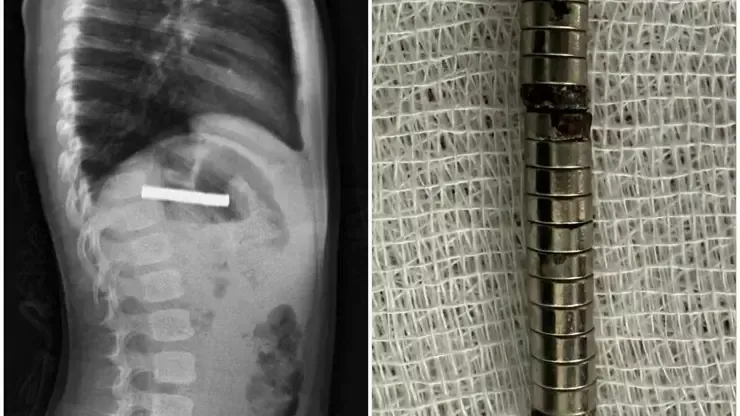

Olay, Erzurum’da meydana geldi. Edinilen bilgilere göre, evde oyun oynayan 3 yaşındaki çocuk, bulduğu 19 küçük mıknatısı yuttu. Bir süre sonra rahatsızlanan çocuk, ailesi tarafından Erzurum Şehir Hastanesi’ne götürüldü.

Burada yapılan tetkiklerde mıknatısların birbirine yapışarak yemek borusunu tıkadığı tespit edildi. Durumun acil olması üzerine çocuk, ambulans helikopterle Elazığ’daki Fırat Üniversitesi Hastanesi’ne sevk edildi.

Fırat Üniversitesi Çocuk Gastroenteroloji, Hepatoloji ve Beslenme Bilim Dalı Başkanı Prof. Dr. Yaşar Doğan ve ekibi tarafından yapılan endoskopik operasyonla, mıknatıslar yemek borusundan mideye alınarak özel bir file yardımıyla çıkarıldı.